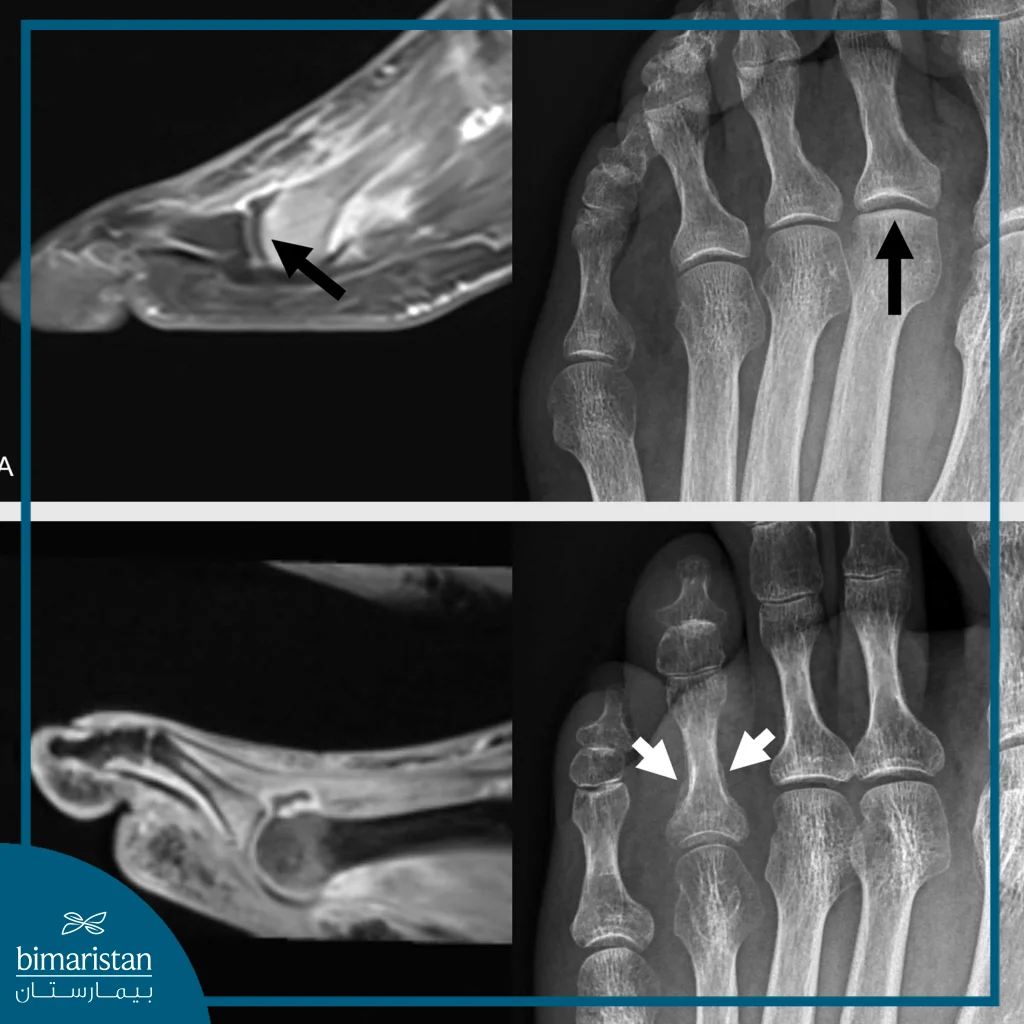

Magnetic Resonance Imaging (MRI)

MRI is employed to evaluate the soft tissues surrounding the bone, including ligaments, tendons, and cartilage. It is also an effective method for detecting stress foot fractures that may not appear on early X‑ray imaging. MRI is indicated when pain persists despite the absence of a clear fracture on conventional radiographs, or when there is suspicion of joint or ligament damage.

X-ray imaging

X‑ray imaging is considered the primary method for diagnosing most cases of foot fractures, as it provides precise visualization of the fracture site and helps determine whether the fracture is closed or open, simple or multiple. It is typically used as the first option following clinical examination and is essential for guiding the physician’s decision regarding immobilization or surgical intervention. In many cases, imaging is performed from multiple angles to obtain a comprehensive view of the bone structure.